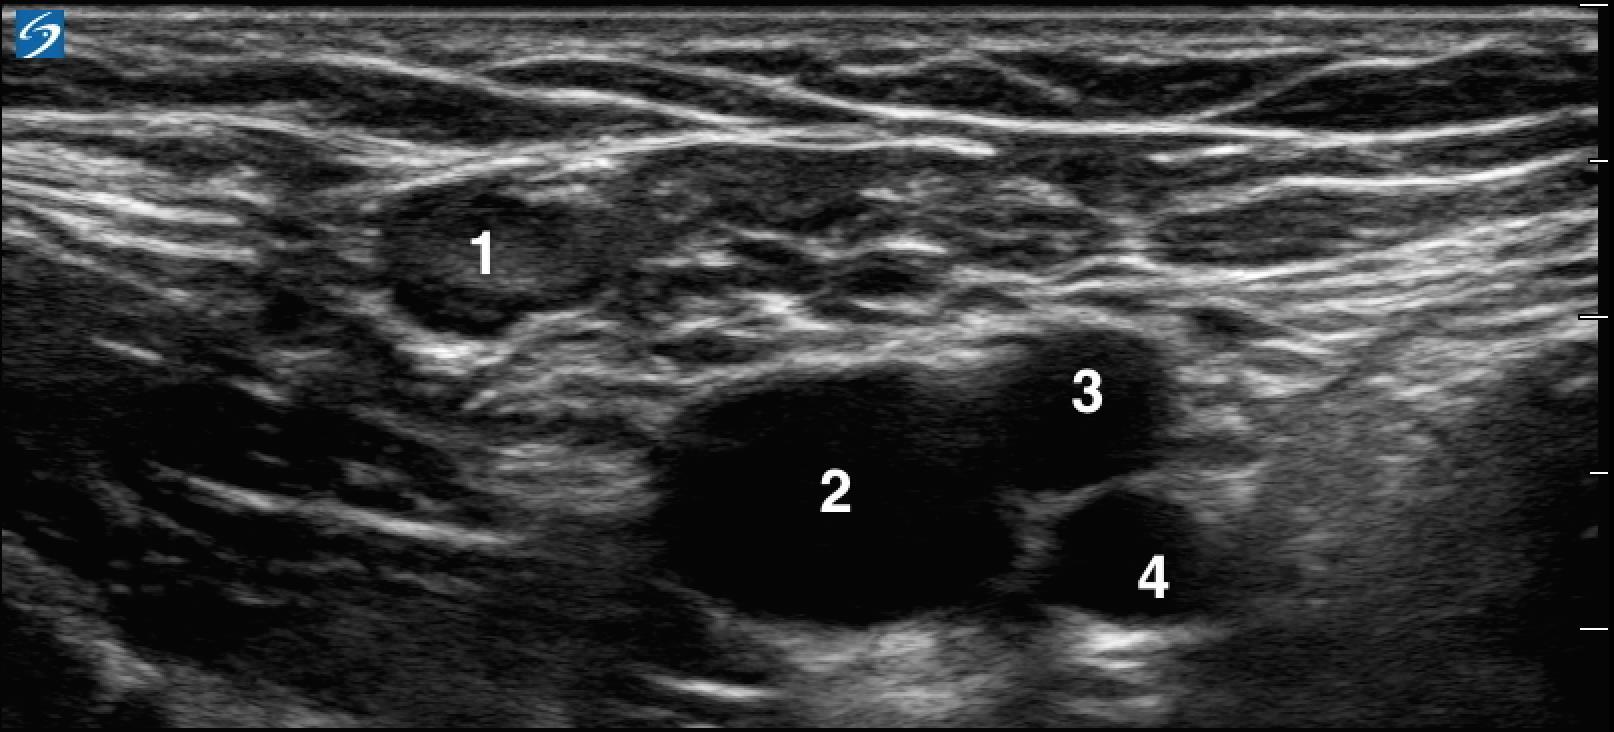

1. Lymph Node

2. Common Femoral Vein (CFV)

3. Superficial Femoral Artery (SFA)

4. Deep Femoral Artery (DFA)